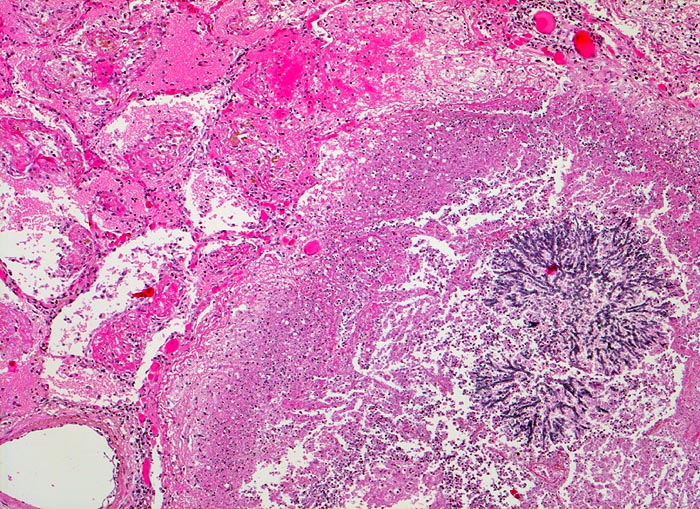

Aspergillus unterscheidet sich von anderen Pilzen (> 1462) (> 712) durch häufige Verzweigungen der Hyphen in einem Winkel von 45°, die radiär in grossen Kolonien liegen (> 547) (> 556). Besonders gut sind die Pilze in der PAS (> 717) und in der Grocott (> 189) Färbung nachweisbar. Die vier häufigsten durch Aspergillen hervorgerufenen Lungenerkrankungen sind die allergische bronchopulmonale Aspergillose, die chronische nekrotisierende Aspergilluspneumonie, das Aspergillom oder wie in diesem Fall die invasive Aspergillose. (Näheres zu den verschiedenen Krankheitsbildern im Literaturlink). Bei Immunsupprimierten invadieren die Pilze häufig die Gefässe. Dies führt zu Infarkten, Blutungen und Nekrosen der Lunge. Über die Invasion der Gefässe kommt es zur septischen Streuung (> 715) (> 49) im grossen Kreislauf.

Morphologische Merkmale:

• Multiple Herde mit zentraler Nekrose und hämorrhagischem Randsaum.

• Pilzmyzelien, zerfallende neutrophile Granulozyten und Erythrozyten im Zentrum der Herde.

• Kräftig gefärbte Pilzhyphen mit 45° Verzweigungen.

• Hämorrhagischer Randsaum um die Nekrose: Hyperämische Alveolarwandkapillaren. Alveolen angefüllt mit Blut, Fibrin und Alveolarmakrophagen.